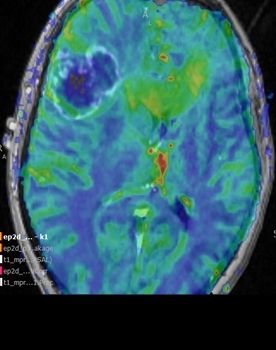

Intraoperative Darstellung der Durchblutung eines Hirntumors und des angrenzenden Gewebes (Perfusion)